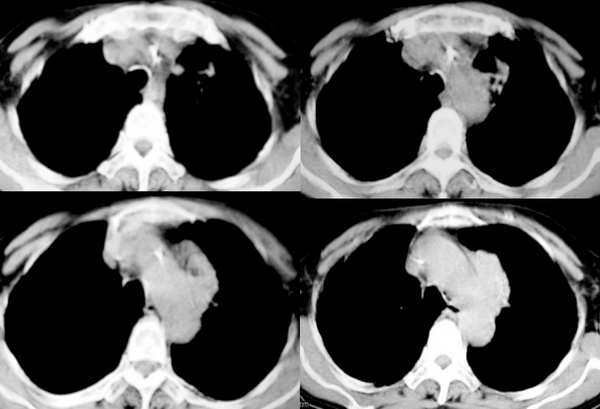

肝内巨大低密度占位,因无增强,就平扫考虑:1.肝血管瘤;2.肝囊肿;肝转移瘤;

郁闷!病灶和主动脉弓是宽基底相连,但主动脉弓壁是清晰可见;肺窗示病灶边缘见不规则毛刺样改变;肝左叶见巨大囊性病灶。我考虑胸部病灶是纵隔型肺癌,肝内病灶不好说是啥。

1、左上纵隔旁型肺癌;

2、左侧横膈抬高,结合临床有声音嘶哑,考虑侵犯纵隔可能;

3、两肺间质纤维化;

4、右肺中叶炎症;

5、肝ⅷ段巨大囊肿。

部分见肝内大圆形低密度灶影,包膜完整,考虑肝囊肿。

纵隔旁软组织密度影,考虑为增大的淋巴结,肝巨大囊肿

因为患者不宜强化,故行b超,报告为肝囊肿。18楼战友说得也有道理,但我想按淋巴引流的途径看{因为肺内炎性病灶主要在右恻}有点不符号,反过来推:如果把它作为淋巴结应该是多个增大淋巴结的融合,但其密度较均匀,未见坏死。{仅供讨论!}谢谢各位战友的!参与!!!